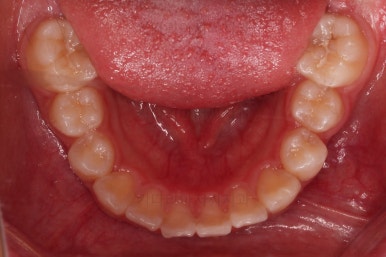

부산소아교정 초진 시 입안의 모습입니다.

윗니가 아랫니보다 많이 앞에 나와있고요.

심지어는 틈새가 벌어지기까지 했습니다.

윗니가 배열 되어있는 U자 형태(그릇 형태)가 아랫니보다 좁은 양상이고요.

이런 앵글씨 2급 부정교합에서는 아랫니가 윗니와 만나기 위해 솟구쳐서 과개교합(아래 앞니가 윗니 뒤쪽으로 깊숙히 올라가 있는 상태)이 나타나기까지 합니다.